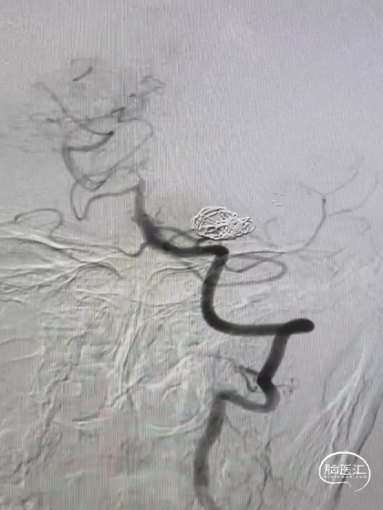

手术过程

Synchro14微导丝牵引支架微导管到位;弹簧圈微导管到位。

送入3*6mm弹簧圈成篮,同时摆一根支架微导管在上干,为T型支架做准备;

释放一枚Leo baby支架 2.5*25mm。

因下干支与M1成角太锐,支架在转弯处打开,多次推拉调整,以“神龙摆尾”方式释放,将支架尾端避开上干开口。

释放支架后,再依次送入2*3mm、1.5*2mm两枚弹簧圈完成治疗。

术后造影显示各分支血管通畅,动脉瘤不再显影。